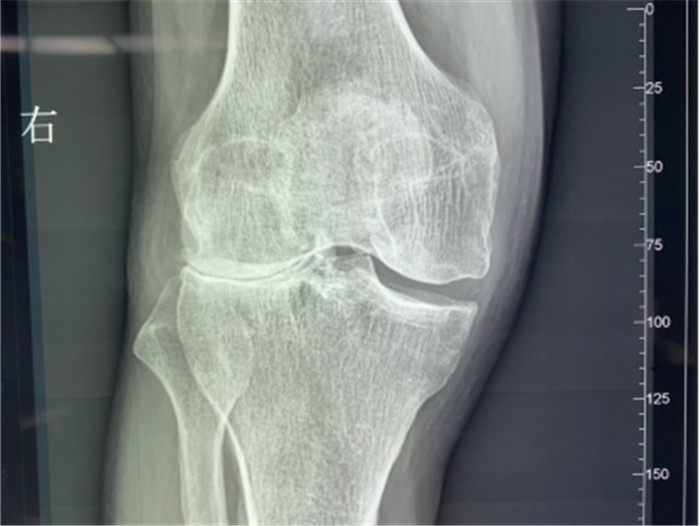

▲右膝關(guān)節(jié)外翻畸形

接診后羅軍主任詳細(xì)檢查病人,發(fā)現(xiàn)病人疼痛癥狀主要集中在膝關(guān)節(jié)外側(cè)間室,右下肢有明顯外翻畸形。這些癥狀都是單髁置換的適應(yīng)癥。雙下肢全長(zhǎng)攝片和右膝內(nèi)翻、外翻位攝片顯示,膝關(guān)節(jié)外側(cè)間隙消失,膝外翻畸形,果不其然印證了上述臨床表現(xiàn)。收治入院后,羅主任團(tuán)隊(duì)決定為患者實(shí)施微創(chuàng)膝關(guān)節(jié)外側(cè)單髁置換術(shù),盡全力為張大爺解除病痛的折磨。